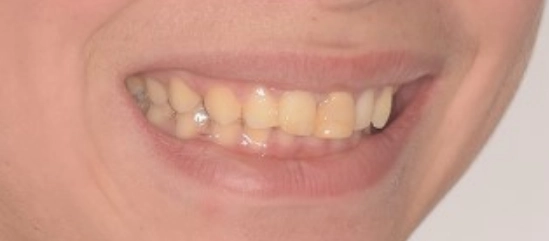

תמונות לפני ואחרי טיפול

אחרי

רק לאחר שהושגו התנאים המתאימים, שולבה שן 21 בתנועה האורתודונטית והובאה בהדרגה למקומה הנכון בקשת. הגישה הזאת אפשרה לטפל קודם במבנה הכללי של הסגר והקשתות, ורק לאחר מכן להפעיל כוחות מחושבים ומבוקרים על השן שנפגעה. לאחר מיקום נכון של השן בתוך הקשת, היה צורך בהחלפת השחזור, כדי להחזיר לשן את העובי, הממדים והמראה האסתטי התקין. שלב זה היה חיוני, משום שגם כאשר מיקום השן נכון אורתודונטית, ללא שחזור מתאים לא ניתן להגיע לתוצאה אסתטית שלמה והרמונית.

בסיום הטיפול התקבלה תוצאה אסתטית ותפקודית ברמה גבוהה מאוד. יחסי הסגר שופרו, הצפיפות נפתרה, הקשתות יושרו, והמראה של האזור הקדמי השתנה באופן משמעותי. מעבר ליישור השיניים, הטיפול הצליח להתמודד עם מצב מורכב של שן קדמית לאחר חבלה, תוך שמירה על זהירות ביולוגית גבוהה ותכנון זהיר של כל שלב. זהו מקרה שממחיש כיצד אורתודונטיה מותאמת אישית איננה רק בחירה במכשור מסוים, אלא היכולת לתכנן את סדר הפעולות הנכון, לשלוט בתנועת שיניים באופן סלקטיבי, להתחשב במגבלות הביולוגיות של כל שן, ולהוביל לתוצאה אסתטית מצוינת גם כאשר נקודת הפתיחה מורכבת במיוחד.